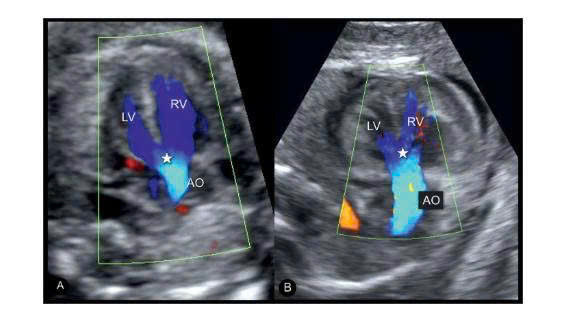

Siêu âm tim thai ngày nay cho phép phát hiện tứ chứng Fallot ngay từ tam cá nguyệt hai, thậm chí sớm hơn trong các trường hợp điển hình.

Một số dấu hiệu trên siêu âm tim thai còn giúp dự đoán trẻ có cần can thiệp ngay sau sinh hay không. Ví dụ hướng dòng chảy qua ống động mạch, kích thước van động mạch phổi, hoặc tỷ lệ đường kính phổi so với động mạch chủ.